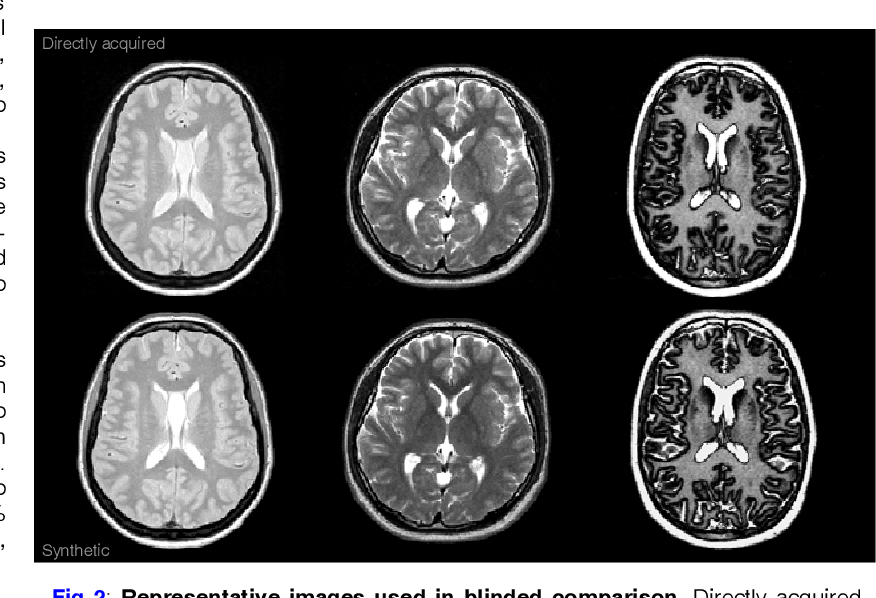

Web if you were to drop back to 3200mhz t1 you should have more stability but what you gain from having t1 you loose from the mhz drop. T1 mri provides excellent anatomical contrast, while t2 mri emphasizes tissue properties and water content. Web breaking down t1 vs t2 mri scan sequences.

Web the t1 technique regulates the rate that protons revert to their regular rotation, and t2 decides the rate at which protons achieve equilibrium or operate at. Find out which tissues are bright. T1 sequences will have grey matter being darker than white matter.

T2 weighted sequences, whether fluid attenuated or not, will have white matter being darker than grey matter. By main room, one means living room, dining room,. Web this page is intended to be a summary and distillation of the arguments that were generated in the debates over speedy deletion criteria t1 and t2.